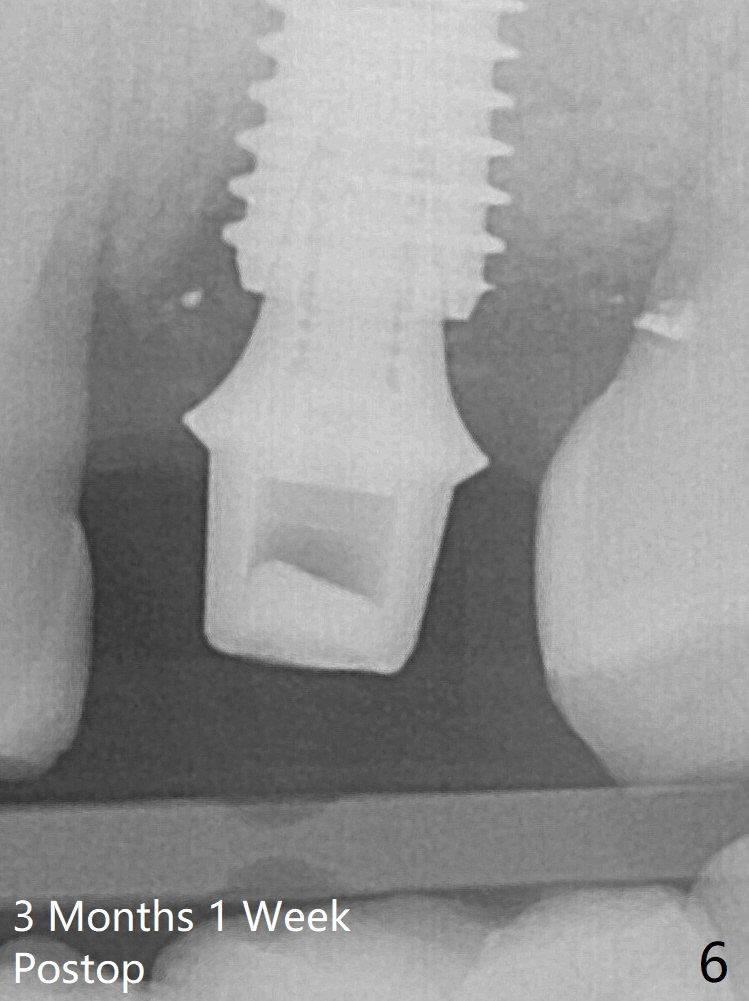

Further pushing of the bone graft from the buccal and palatal socket gaps results in more ideal packing (Fig.5 >). If the bone graft were placed first, packing would have been easier. An immediate provisional is fabricated to prevent further mesial shifting of the 3rd molar (Fig.1 arrow). The implant remains stable, while the provisional and abutment are loose 3 months 1 week postop (Fig.6). Impression is taken after abutment cleaning and retightening.